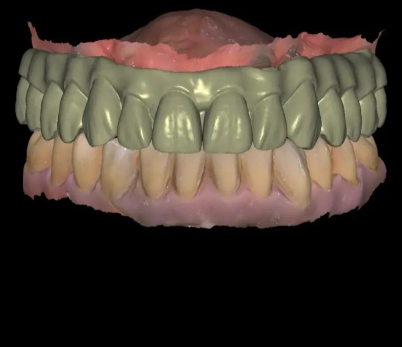

La resina de ESUN es un diseño especial creado específicamente para aplicaciones dentales, lo que garantiza una alta precisión y una superficie suave. Además, es libre de cenizas, lo que resulta ideal para el proceso de casteo. Presenta una alta dureza y es resistente al impacto, lo que mejora la durabilidad del producto final.

En el proceso del testeo de la resina castable ESUN encuentro que es fácil para calibrar y el nivel de detalle de la impresión la verdad que me sorprendió, incluso se puede ver en la foto del casquete impreso lo nítido del borde del hombro.. y para terminar algo que puede parecer no tan importante, el envase de aluminio en el que viene la resina ESUN es lo más!

El acabado es excelente, no deja cenizas por lo que es ideal para hacer moldes de "cera" perdida, la primera impresión de las piezas es curiosa, a primera vista no difiere demasiado de una resina estándar por lo que de ser necesario se podía usar para impresión en modelos y demás. Requiere un poco más de tiempo de exposición y al ser un poco menos viscosa le podes subir un poco la velocidad de la bandeja.